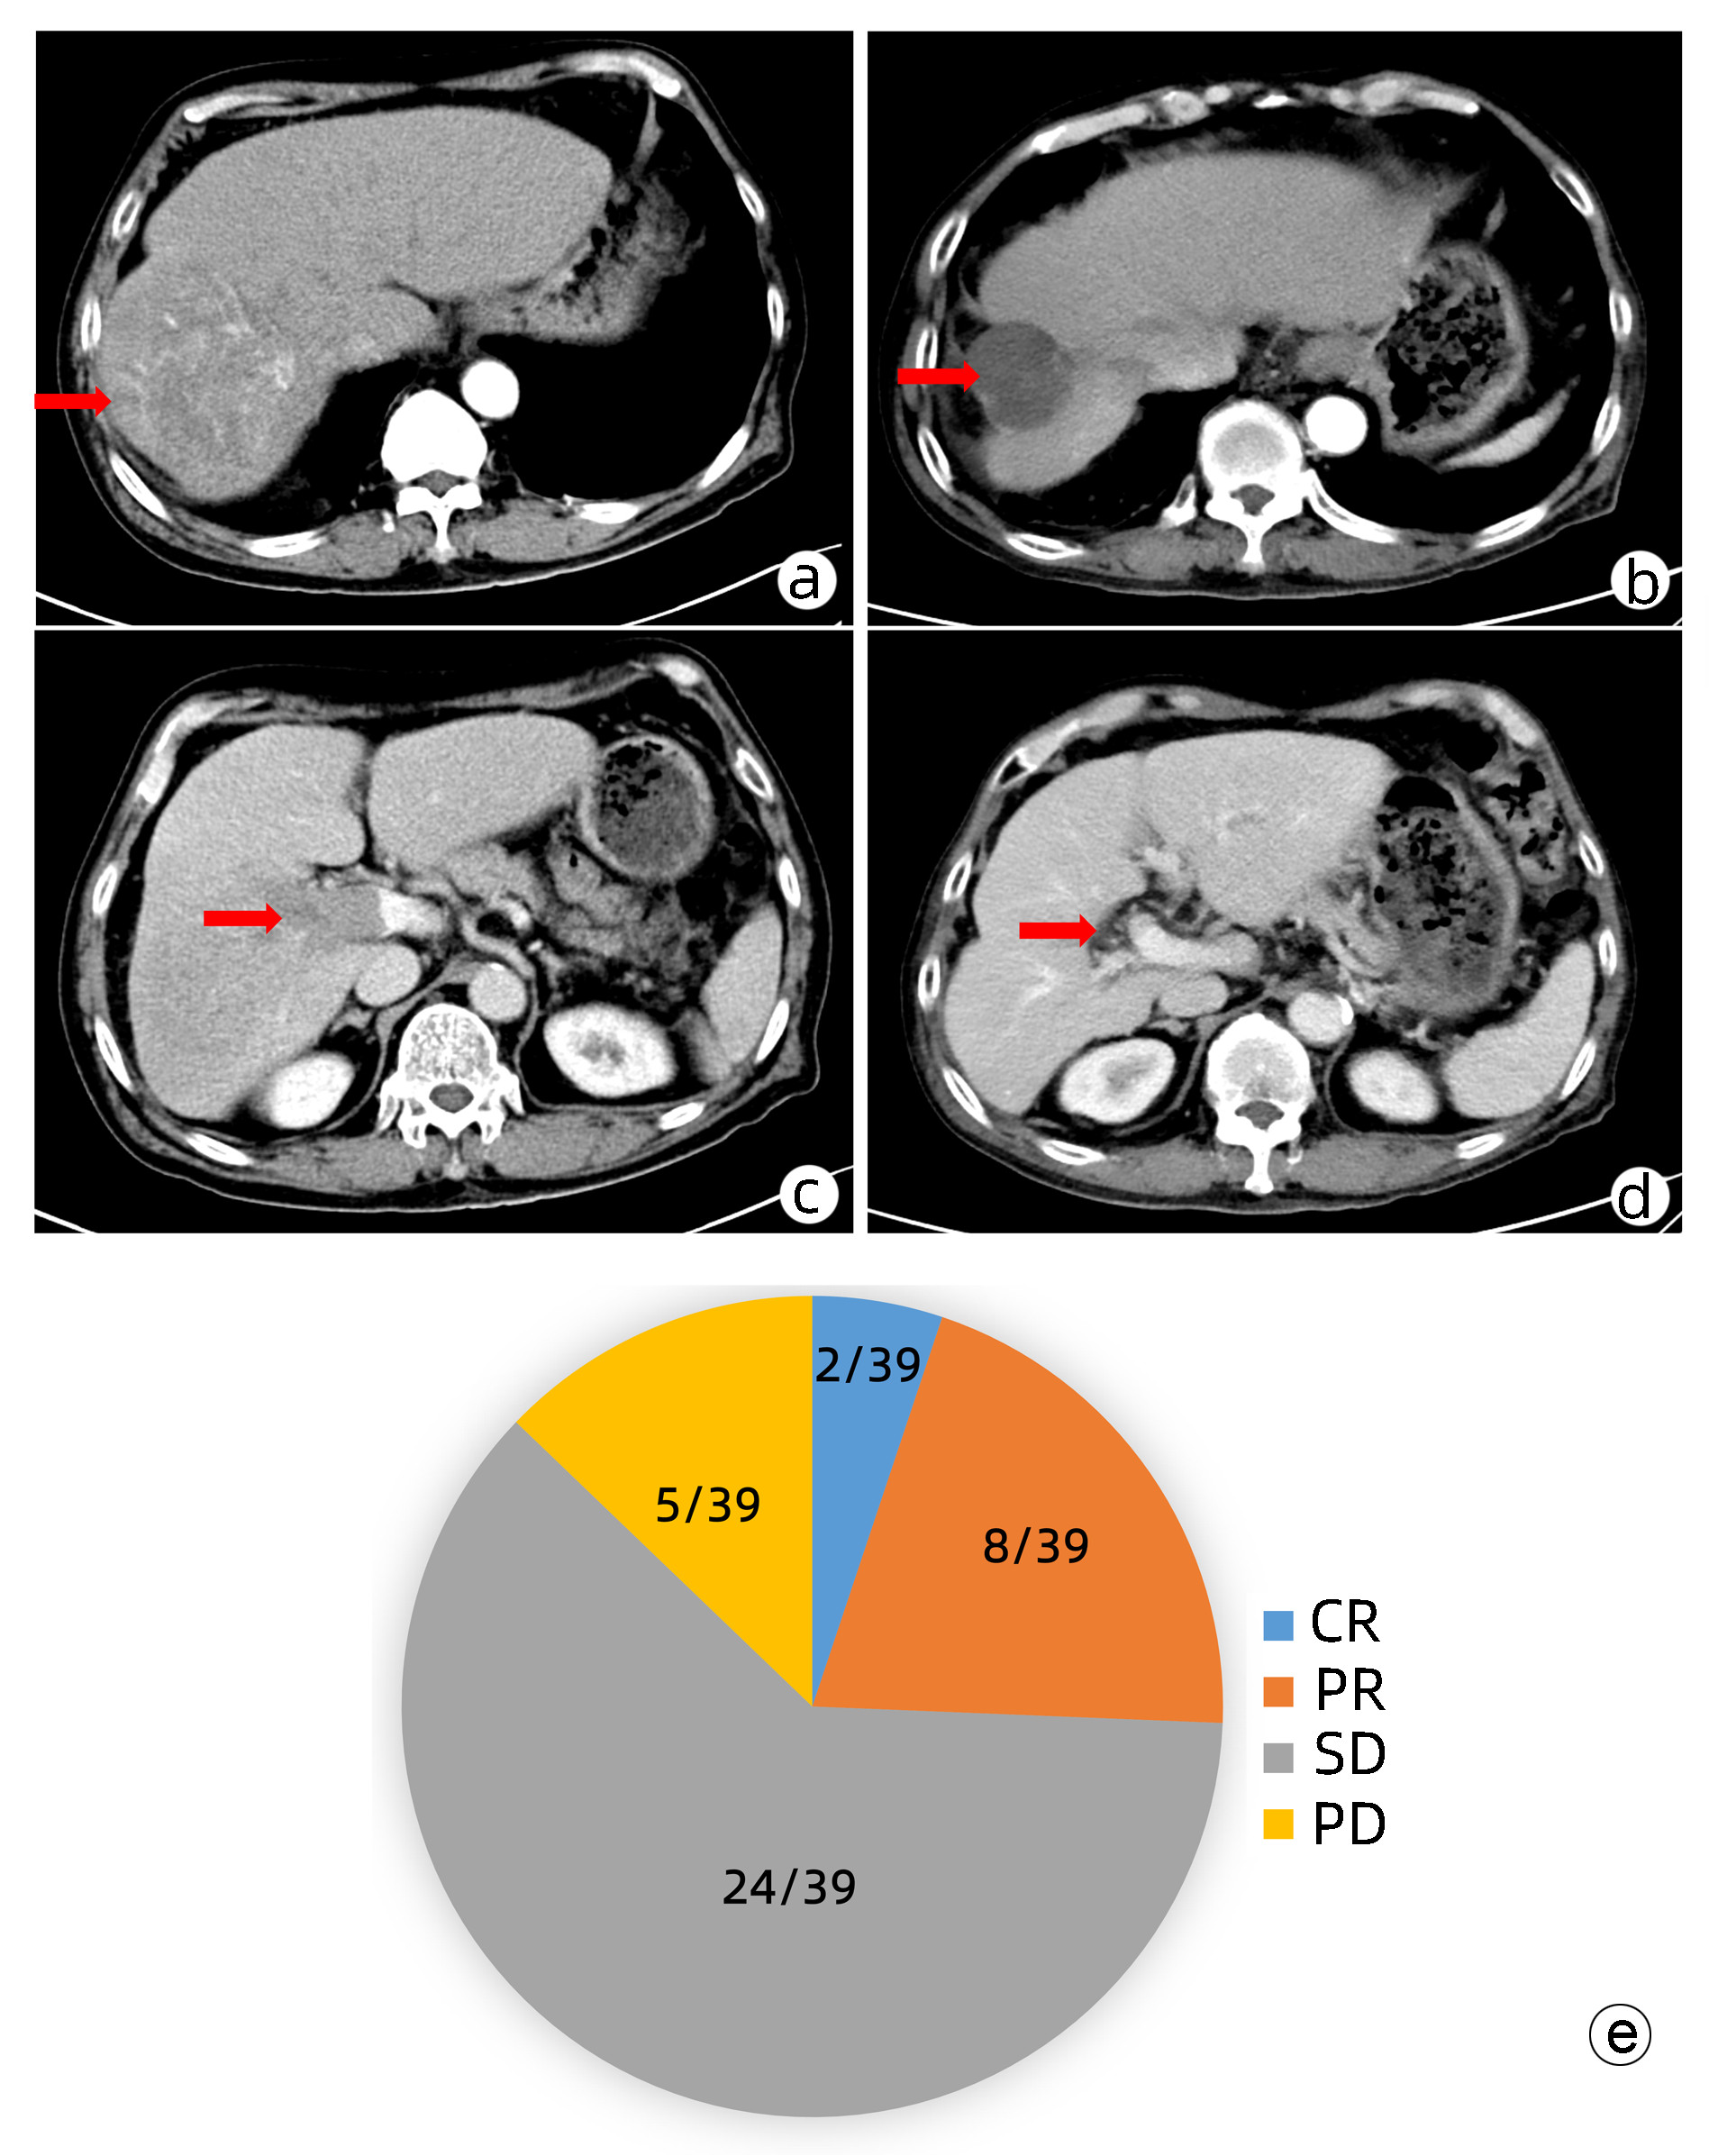

肝动脉灌注化疗及其综合治疗方案对中晚期肝细胞癌患者的临床疗效及预后因素分析

戴文聪, 臧梦雅, 袁国盛, 李祺, 李榕, 李文利, 董书语, 陈锦章

2023, 39(7): 1592-1599. DOI: 10.3969/j.issn.1001-5256.2023.07.013

摘要(1476) HTML (1025) PDF (2254KB)(92)

摘要:

目的  本研究旨在观察FOLFOX方案持续肝动脉灌注化疗(HAIC)及其综合治疗方案对中晚期肝细胞癌患者的临床疗效并分析影响预后的因素。  方法  回顾性收集南方医科大学南方医院2018年9月—2021年11月行FOLFOX方案持续HAIC的66例中晚期肝细胞癌患者临床资料。观察治疗后患者的客观缓解率、疾病控制率、中位无疾病进展生存时间(mPFS)和中位生存时间(mOS)并记录治疗相关不良反应。针对伴有门静脉癌栓的患者,评价治疗对门静脉癌栓的疗效。采用Kaplan-Meier法进行生存分析。采用Cox回归分析影响预后的因素。  结果  按照RECIST1.1标准,FOLFOX-HAIC及其综合治疗方案治疗66例中晚期肝细胞癌患者的客观缓解率和疾病控制率分别为33.3%(22/66)、86.4%(57/66),mPFS和mOS分别为8.2个月和22.1个月。其中39例合并门静脉癌栓的肝癌患者中完全缓解2例,部分缓解8例,稳定24例,进展5例。客观缓解率为25.6%(10/39),疾病控制率为87.2%(34/39)。不良反应主要为消化道反应16.7%(11/66)、发热12.1%(8/66)、肝区疼痛10.6%(7/66)、骨髓抑制3.0%(2/66)和造影剂过敏3.0%(2/66)。无Ⅳ级以上的毒副反应。无并发症导致的死亡。Cox分析显示肝外转移(HR=2.668, 95% CI:1.357~5.245)和凝血酶原时间(HR=1.282, 95%CI:1.080~1.630)是影响患者PFS的独立危险因素(P值均<0.05), AST水平(HR=1.008, 95%CI:1.002~1.013)和凝血酶原时间(HR=1.303, 95%CI:1.046~1.630)是影响患者OS的独立危险因素(P值均<0.05)。  结论  FOLFOX-HAIC及其综合治疗方案治疗中晚期肝细胞癌有一定的疗效,不良反应可控。